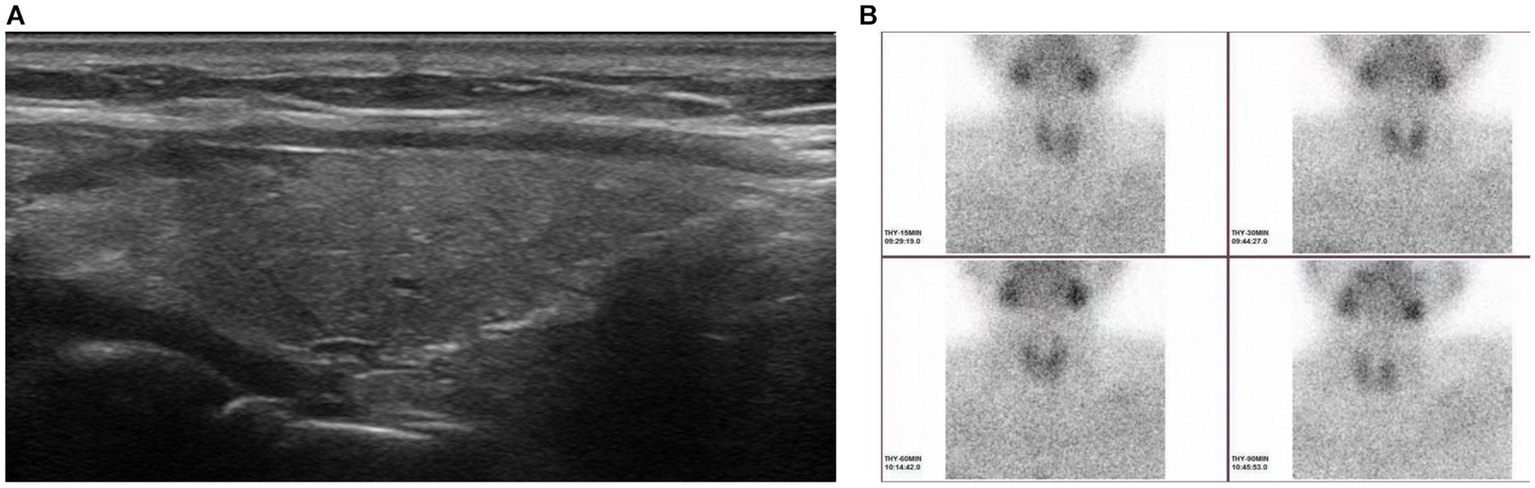

Clinical data, including the levels of serum iPTH and calcium, were collected in the subsequent follow-up (1 day, 1 week, 1 month, 3 months, 6 months and 12 months after ablation). As shown in Figure 2, the levels of serum iPTH and calcium decreased to 10.3 pg./mL and 2.8 mmol/L after 1 day. And the symptoms of nausea and vomiting released significantly as well. After 1 week, the levels of serum iPTH and calcium stayed within normal range (21.2 pg./mL and 2.41 mmol/L, respectively). After 1 month, the level of serum iPTH slightly increased to 46.9 pg./mL, but it still belonged to normal range. The level of serum calcium remained within normal range, with 2.3 mmol/L. After 3 months, the levels of serum iPTH and calcium remained stable (43.48 pg./mL and 2.29 mmol/L, respectively). The rest of the pregnancy went uneventfully and a healthy baby boy was born by cesarean section half 1 year after ablation. The tests demonstrated that both of mother and her baby had normal serum calcium (2.35 and 2.31 mmol/L, respectively). The iPTH and calcium of the patient were remaining within normal ranges during follow-up (6 months, 43.48 pg./mL and 2.28 mmol/L; 12 months: 43.95 pg./mL and 2.25 mmol/L). One year later, it was surprised that ultrasound revealed the primary hypoechoic area (parathyroid adenoma) disappeared (Figure 3A). Furthermore, 99mTc-methoxyisobutylisonitrile (99mTc-MIBI) confirmed no hyperplastic parathyroid in both the early and delayed phases (Figure 3B).

Figure 3

Ultrasound showing the primary hypoechoic area (parathyroid adenoma) disappeared 1 year after microwave ablation (A). No hyperplastic parathyroid was found in both the early and delayed phases (15, 30 and 60 min after the injection of methoxyisobutylisonitrile) when 99mTc-methoxyisobutylisonitrile was performed 1 year after microwave ablation (B).